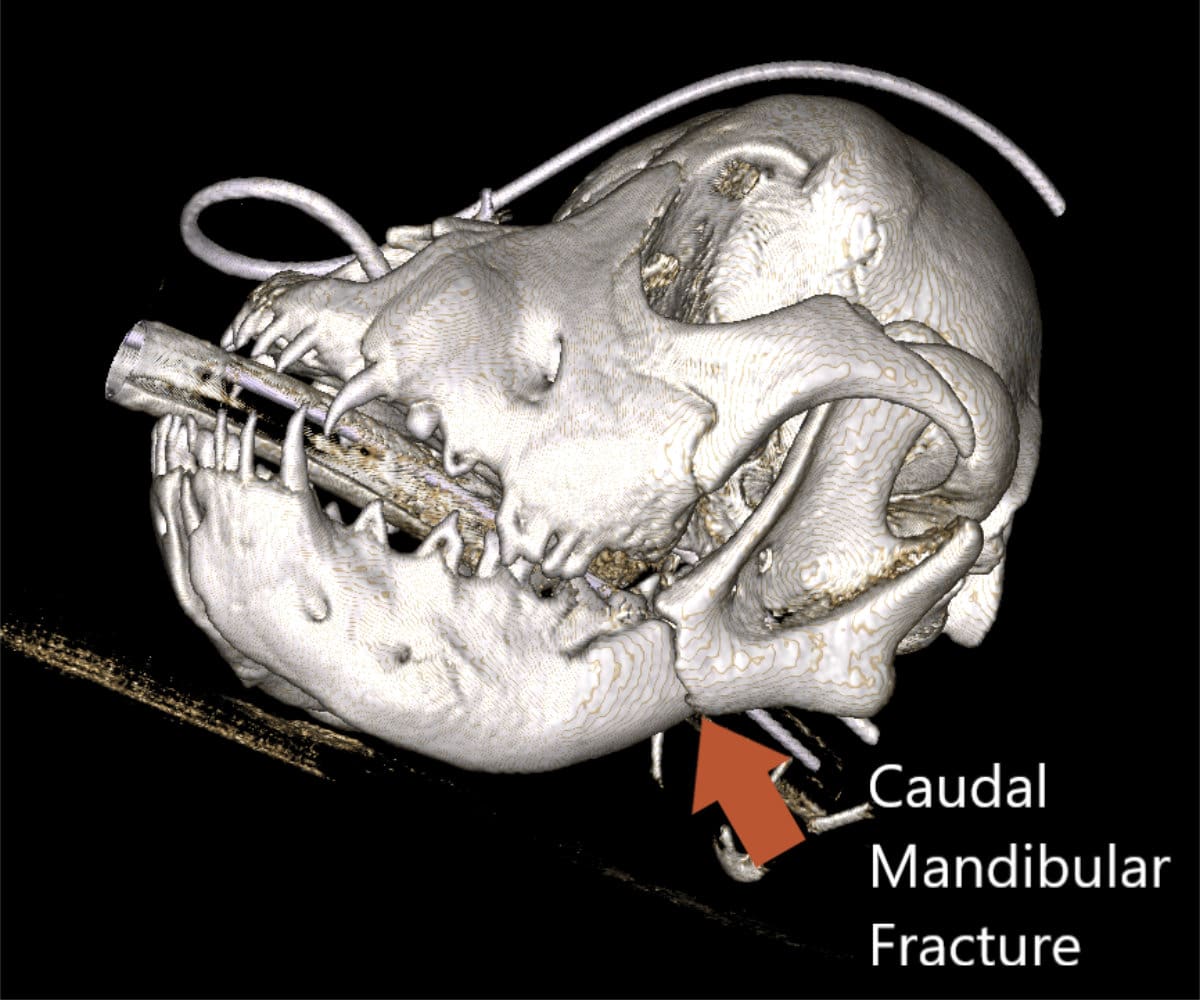

The advantages extend beyond diagnosis, as CBCT enables intricate 3D reconstructions of the skull, providing invaluable support to our doctors in the meticulous planning process for facial plating procedures.

Our CBCT VetCAT unit is easily rolled up to our treatment table and takes only 40 seconds to complete a scan. It has proven to be invaluable in the diagnosis and treatment planning for pets with periodontal, endodontic and cancerous disease conditions. It is also indispensable in the evaluating our trauma cases with jaw fractures.